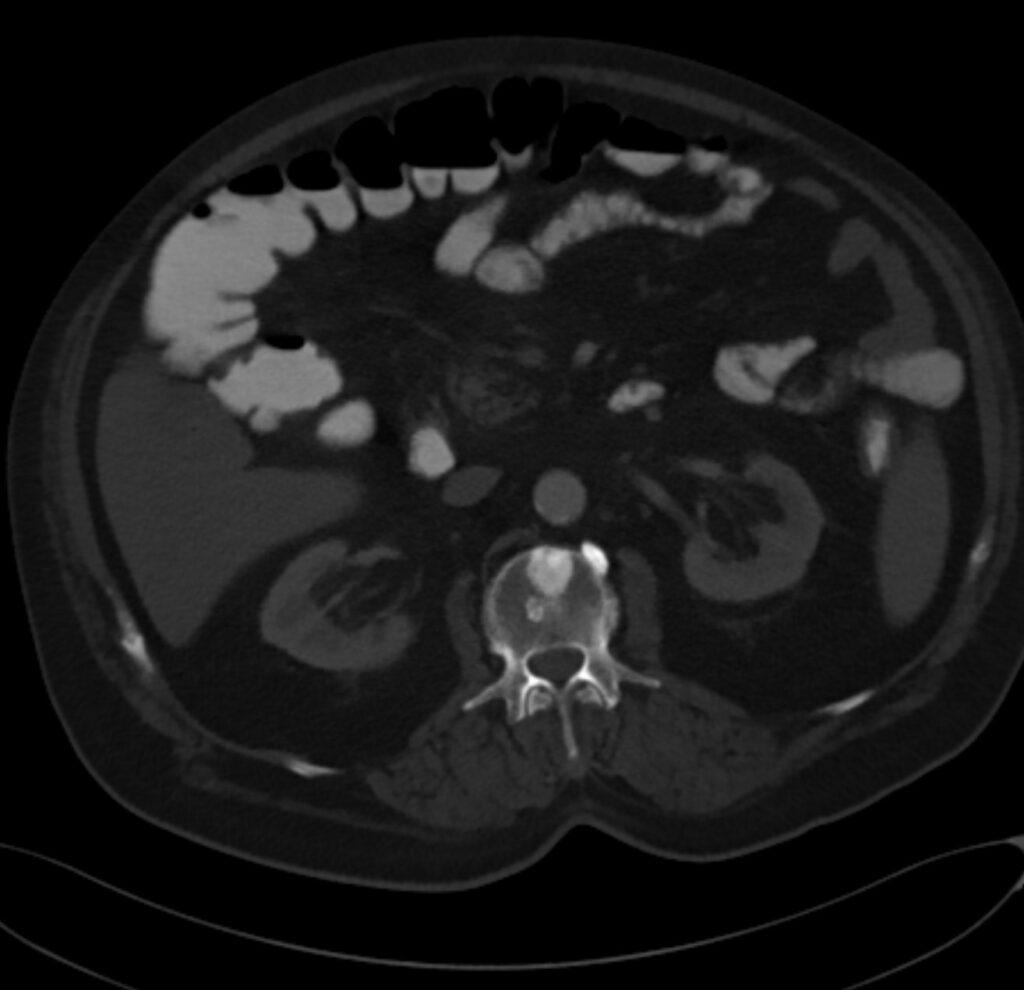

*73-year-old male present with bone pain.

What is the most likely diagnosis?

Sclerotic bone metastases (prostate carcinoma)

CT images revealed sclerotic bone metastases.